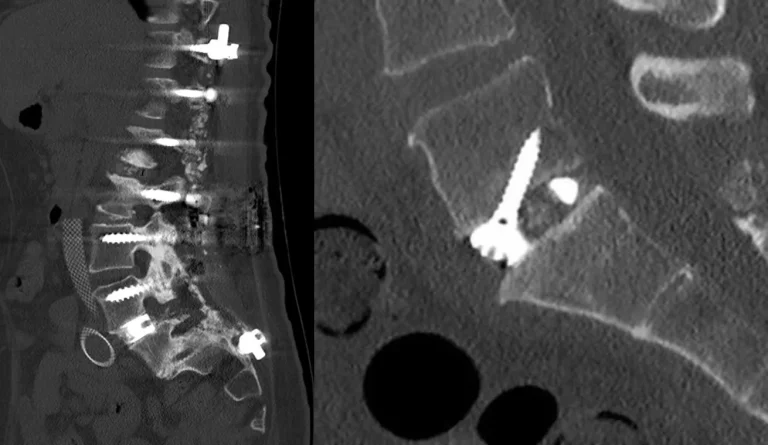

CT scan showing spinal instrumentation with screws and rods in place.

Hardware Failure

Screw loosening, broken screws or rods, and cage migration requiring revision surgery.